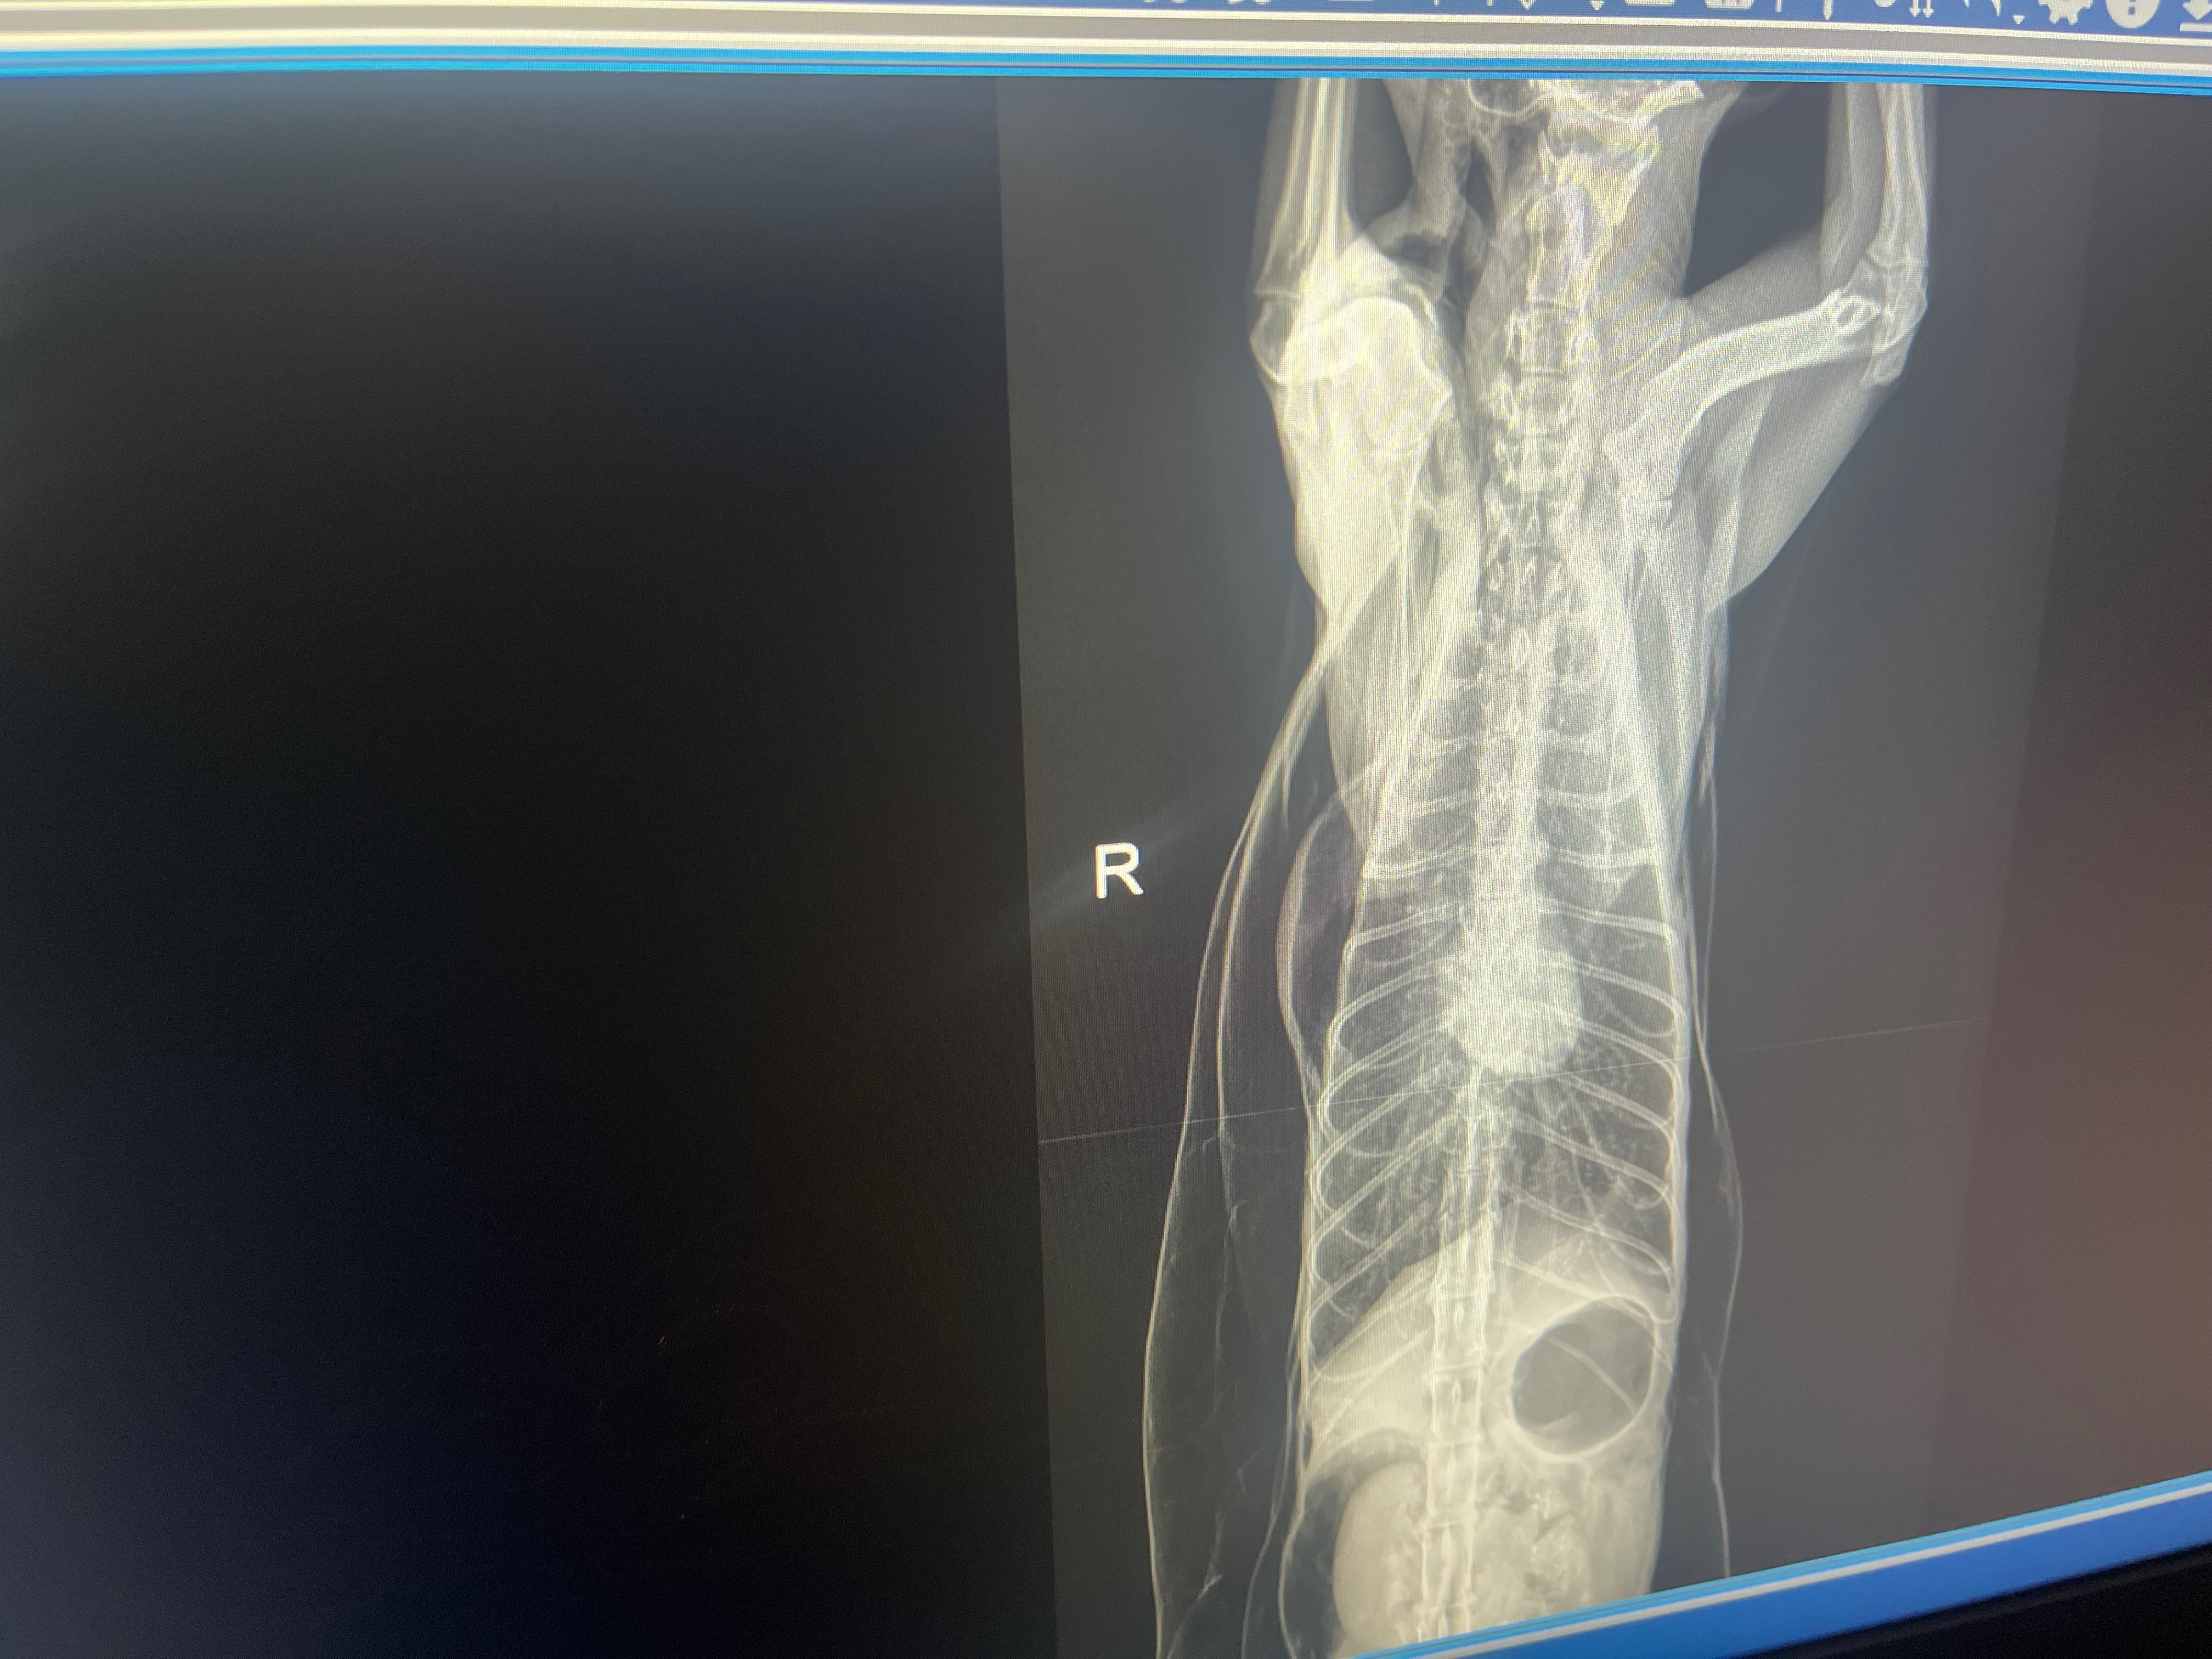

Hello anybody who reads this on 6-12-25 I had to suddenly put down waffles, she was a rescue I found outside with her sister chicken, when I got home from work she was laying in the corner not breathing right and swollen, I took her to the vet and she found pockets of gas spread throughout her entire body crushing her lungs. I had to make a sudden choice to put her to sleep, I’ve never made one of these before but I hope you can spare $5 or anything to help me out, I thank you so much to anyone who spends the time to read this and donate. I used my rent money to ease her pain and I’m in a Financial hard spot currently but I couldn’t let her suffer, thank you again